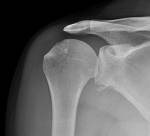

Shoulder dislocation

- anterior >95%

- subcoracoid (majority)

- subglenoid (1/3)

- subclavicular (rare)

- posterior 2-4%

- inferior (luxatio erecta) <1%